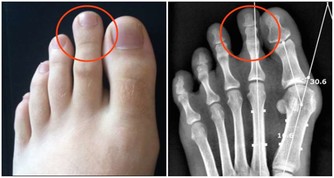

2.4 減少癌症風險

部分研究指出,定期捐血與降低某些癌症(如肝癌與肺癌)風險之間存在一定關聯,特別是體內鐵含量偏高者。